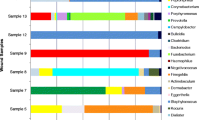

Of the 26 bone samples that grew pathogens with conventional culturing techniques, three did not sequence. The three samples that did not sequence grew Stenotrophomonas maltophilia (n = 1), S. aureus (n = 1) and Enterobacter cloacae (n = 1) with conventional culturing. All three samples were monomicrobial infections. Table 1 presents an overview of all the genera that were sequenced and occurred in at least 21.7 % (5 of 23) of the positive bone samples. The table includes the average contribution of each genus to the total bacterial population in those samples as represented as a percentage. Staphylococcus spp. were the predominant genus identified in the positive bone samples. Sequences of Staphylococcus spp. were detected in 20 of the 23 samples, with an average contribution of 28.6 % to the total bacterial population. The most prevalent populations of Gram-positive cocci identified after that were, in order, Corynebacterium (n = 18), Streptococcus (n = 13) and Propionibacterium spp. (n = 11). Facultative anaerobes included Actinomyces and Helcococcus spp. in 6 and 5 of the samples, respectively. Obligate anaerobes such as Peptoniphilus, Finegoldia, Anaerococcus, Clostridium, Porphyromonas and Prevotella were detected in 17, 15, 12, 9, 7 and 5 of the samples, respectively. Two of the positive samples were low coverage samples (sequence counts of 9 and 534, respectively). Both of these low coverage samples only had sequences that matched with Staphylococcus spp. and grew coagulase-negative staphylococci with conventional techniques.

Table 2 presents a comparison of the results of both culturing techniques. Only the genera that occurred in at least 21.7 % (5 of 23) of the positive bone samples with the sequencing method are reported. With 16S rRNA sequencing, we found significantly more anaerobic pathogens (86.9 % vs. 23.1 %, p = 0.001), significantly more Gram-positive bacilli (78.3 % vs. 3.8 %, p < 0.001) and more polymicrobial infections (91.3 % vs. 64.0 %, p = 0.125). Also, greater bacterial diversity was seen both in the Gram-positive cocci and the anaerobes.

No pathogens were identified in 8 out of the 34 bone samples (23.5 %) with conventional culture techniques. Two out of those eight negative samples did not sequence either. The genera that were sequenced in the remaining six and occurred in at least 33.3 % (2 of 6) of the samples are presented in Table 3. Staphylococcus spp. were detected in all of the negative samples, with an average contribution of 21.8 % to the total bacterial population. One of the negative samples was a very low coverage sample (sequence count 3); all three sequences matched with the Staphylococcus spp. sequence derived from the NCBI database. This was the only negative bone sample that had a single genus present.